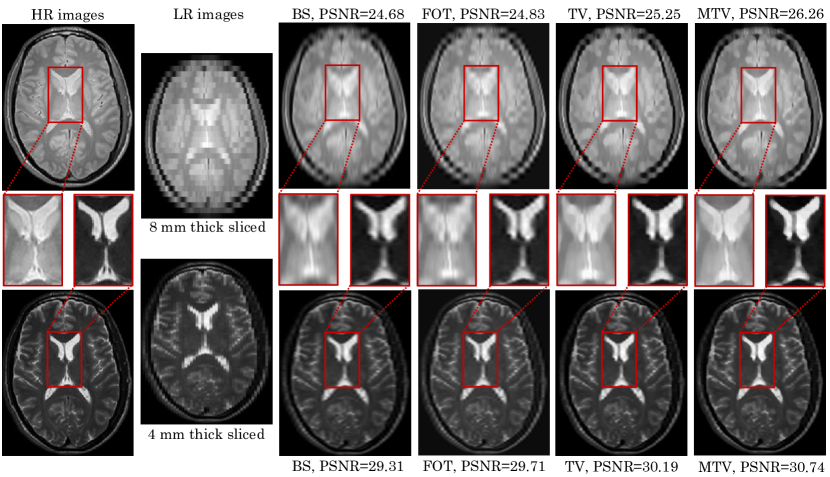

Figure 3: Two LR images were simulated from two HR images (PD- and T2-weighted) and then reconstructed using four methods. BS, FOT and TV are single-modality SR techniques, capable of combining LR images of only one MR contrast. MTV on the other hand, uses information from both MR contrasts.

The proposed model was validated on the IXI dataset. LR images were generated from HR images allowing for ground-truth comparisons. The peak signal-to-noise ratio (PSNR), root-mean-square error (RMSE) and dice score were used to quantify the findings. Four methods for obtaining estimates of the unknown HR images were used. One interpolation based, using cubic b-splines (BS); three MAP based, using first-order Tikhonov (FOT), TV and MTV regularisation. FOT regularisation was achieved by changing the prior in (5) accordingly. Figure 3 shows an example of simulating LR images from HR images, and subsequently estimating the HR images from the LR ones using the different methods.